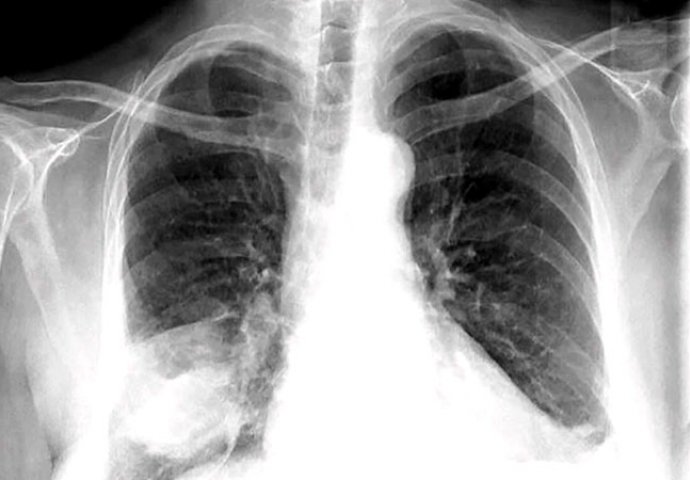

Sumnju na upalu pluća pobuđuje klinička slika, a potvrđuje ju RTG pluća. RTG pluća gotovo uvijek pokazuje neki stupanj infiltracije.

Kod imunokompromitiranih te kod ljudi koji su bili izloženi određeni uzročnicima nakon negativnog RTG-a učinit će se CT kako bi s većom sigurnošću mogli isključiti upalu pluća. Može se također vaditi krv iz koje se određuje razina bijelih krvnih stanica čiji broj se najviše povećava kod bakterijske infekcije. Budući da upala pluća može dovesti do smanjene razine kisika u krvi određivanje iste također može biti korak u dijagnostici.

Većini pacijenata sa poboljšanjem kliničke slike nije potreban kontrolni RTG. Kontrolni RTG treba uraditi 7 do 12 tjedana nakon liječenja kod bolesnika starijih od 50 godina, posebno kod muškaraca te kod pušača.

RTG nije nužan kod djece koja se liječe ambulantno, ali trebao bi se uraditi kod djece s težim oblikom bolesti, komplikacijama, ponavljajućim upalama pluća te kod klinički atipičnih oblika bolesti.